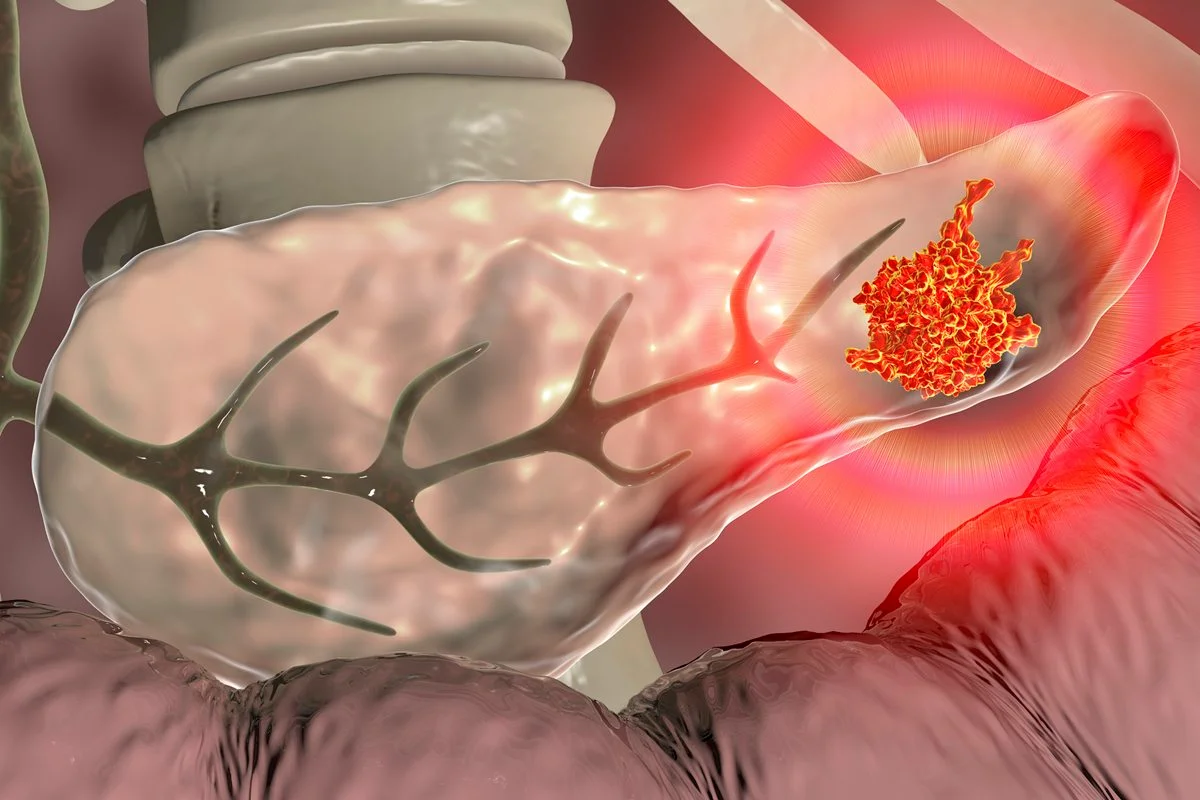

Alguns alimentos prejudicam o órgão

Kateryna Kon/Science Photo Library